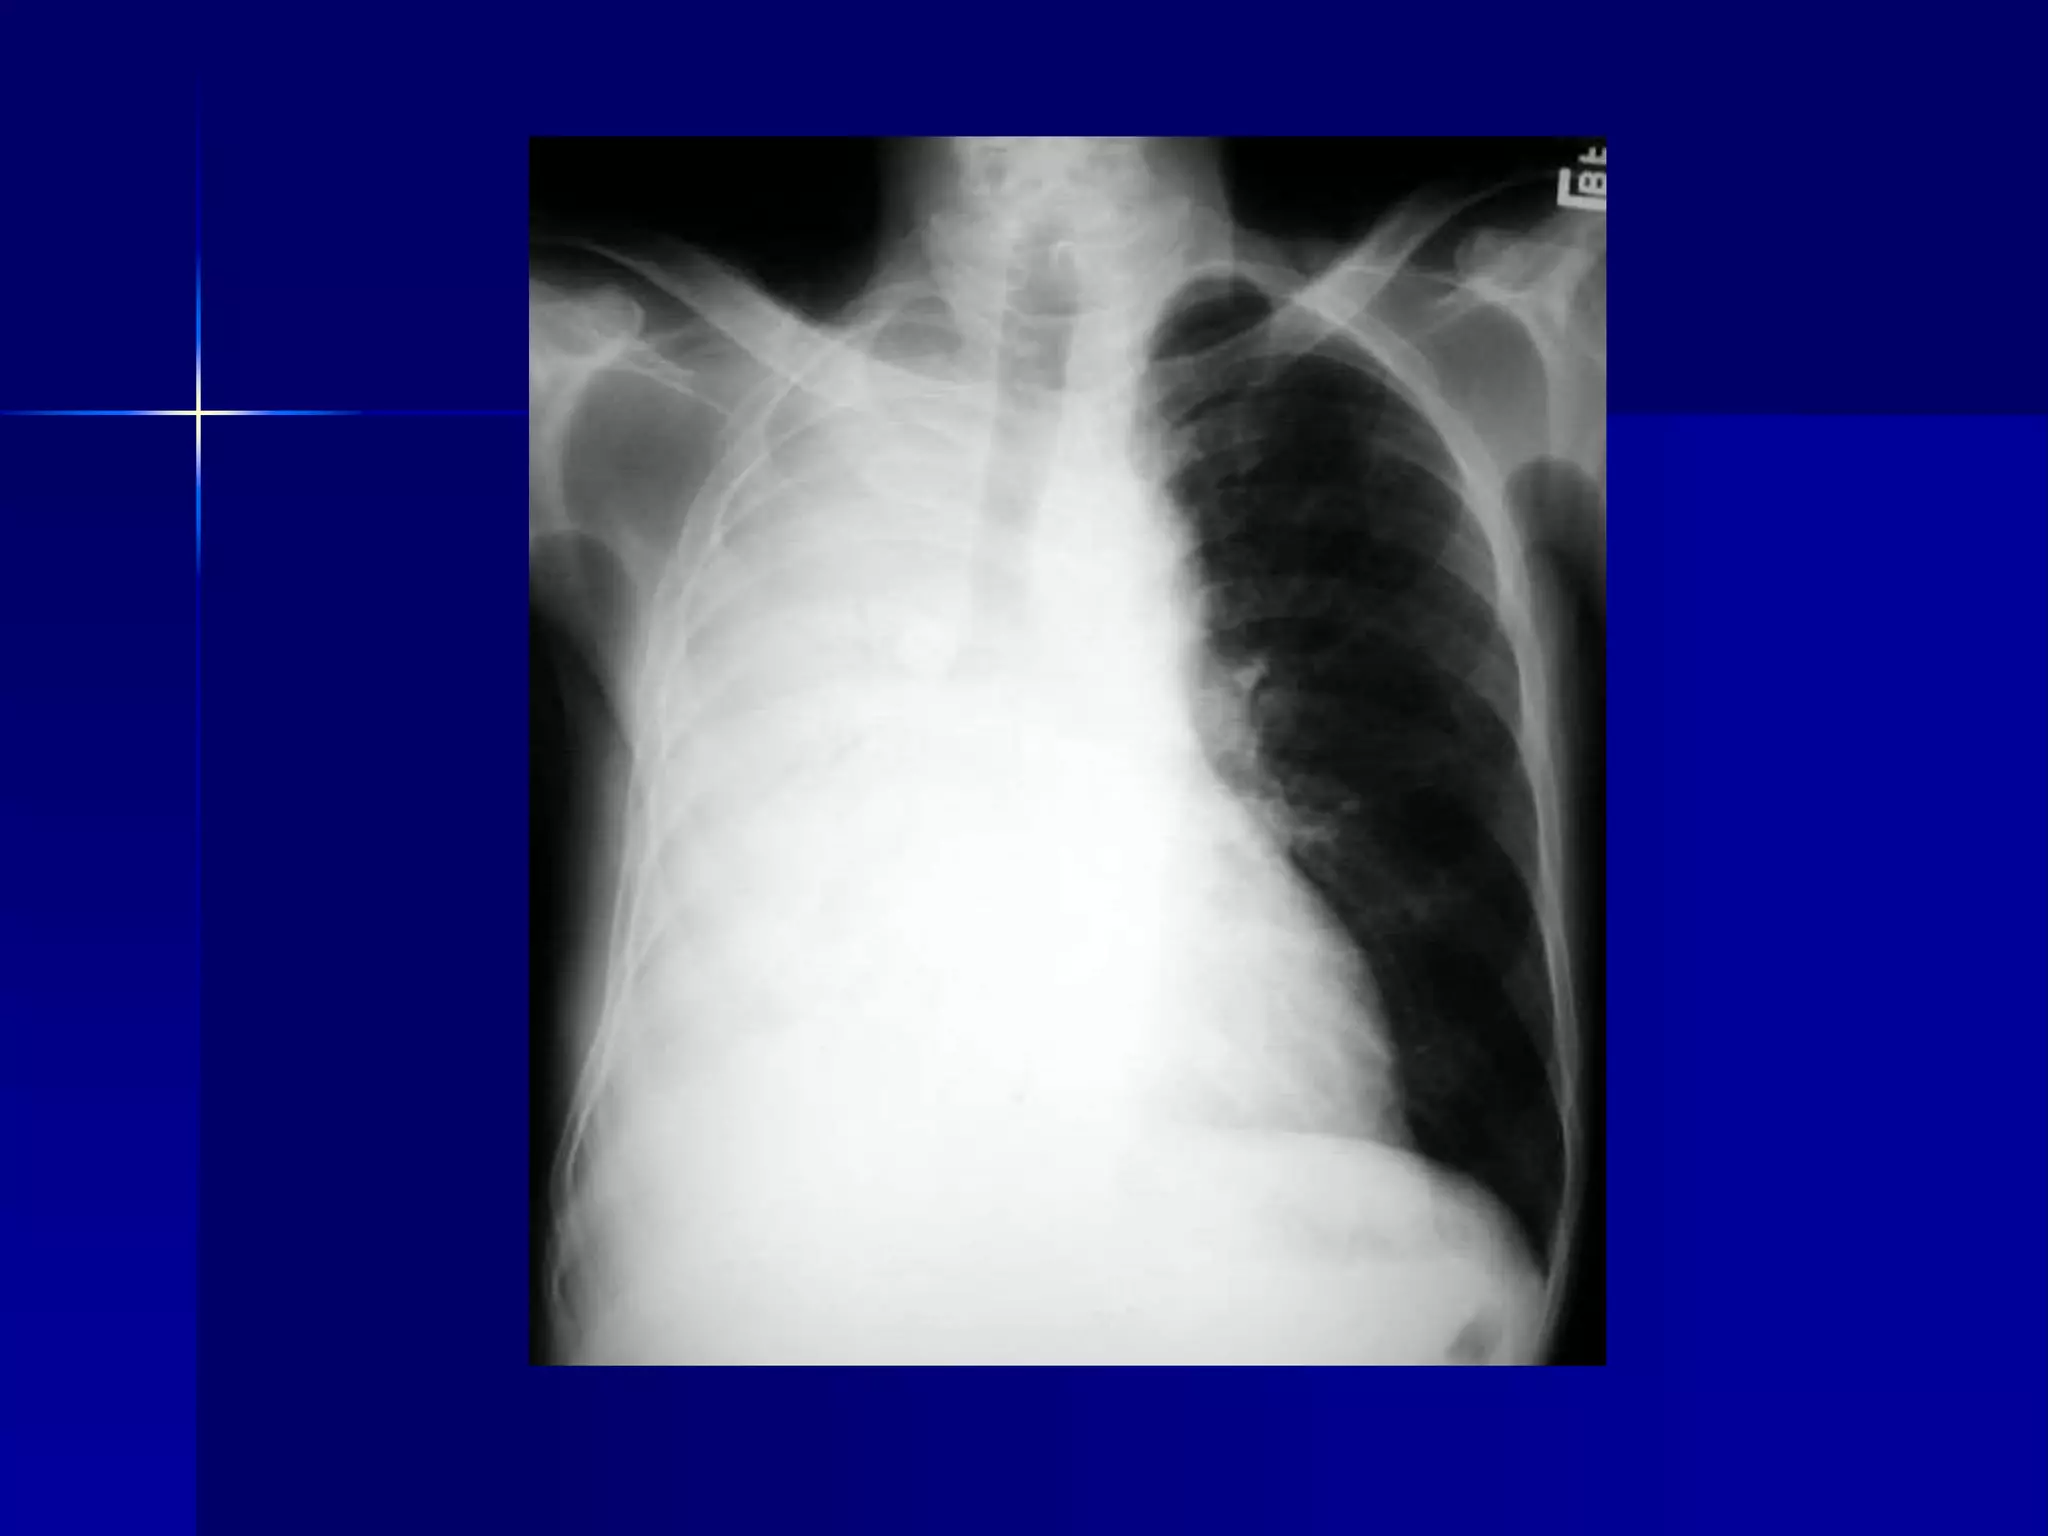

 Atelectasis Right Upper Lobe

 Density in the right upper lung field

 Transverse fissure pulled up

 Right hilum pulled up

 Smaller right lung

 Smaller right hemithorax